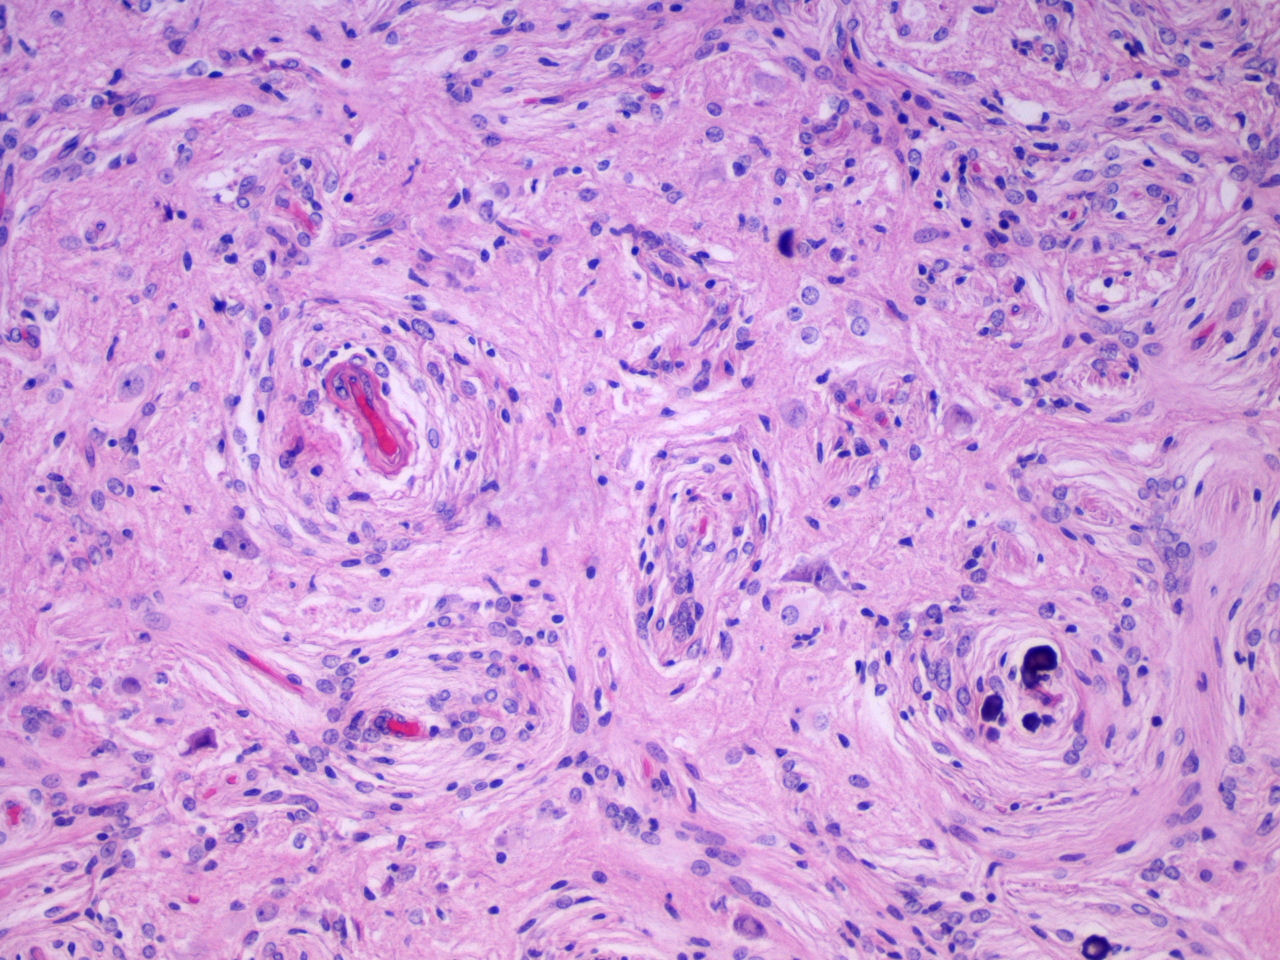

Fig. 5. Proliferación vascular rodeada de cels.meningoteliales que se extiende en el cortex cerebral, con distintos grados de fibrosis. H-Ex100, T. de Masson x 200 Fig. 6. Vasos de pequeño tamaño, con paredes hialinizadas rodeados concentricamente de cels. meningoteliales. El fondo está constituido por celularidad glioneuronal. H-Ex200